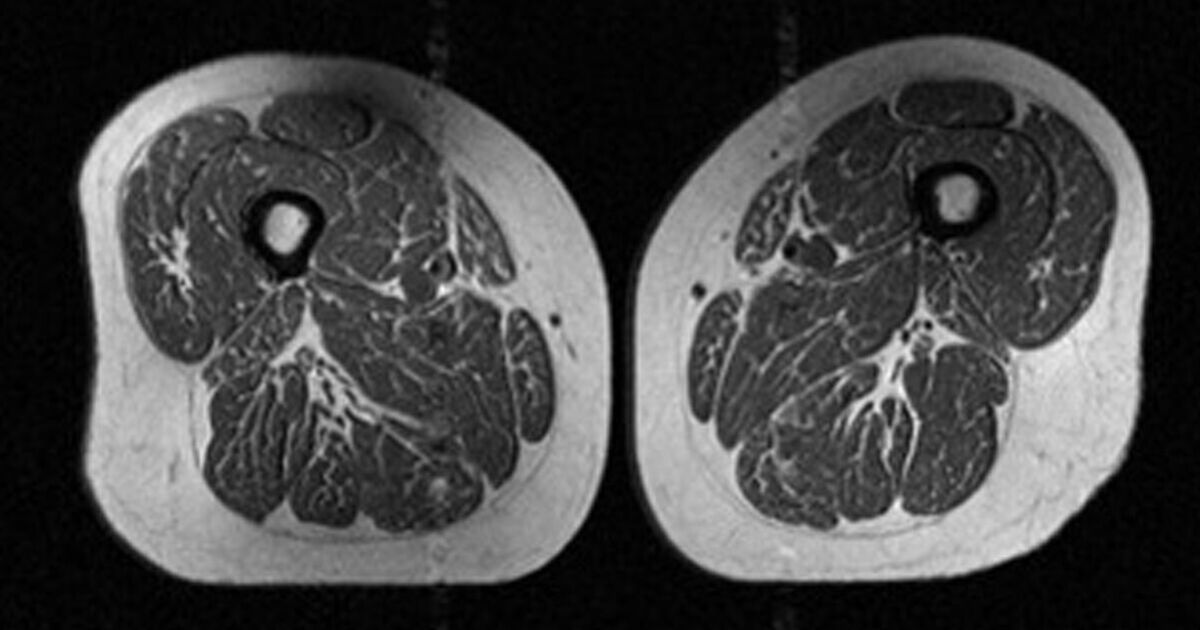

X-ray photographs of a woman’s thigh published in a newly released study show how ultra-processed foods negatively impact the body.

A report in the RSNA Journal reveals how ultra-processed foods impact the human body (Image: RSNA Journal)

The authors published X-ray photographs of a 62-year-old woman’s leg used for research purposes, providing a visual aid of how ultra-processed food consumption manifests in the body.

Researchers revealed that 87% of the woman’s diet consisted of ultra-processed foods, including cold cereals, chocolate candy bars and soda, and that she participates in moderate amounts of exercise.

However, the high levels of ultra-processed foods in her body still led to a “marbling” effect, where fat accumulates and replaces healthy muscle tissue with weaker ones.

The increased fat accumulation puts her and thousands of others like her at greater risk of metabolic disease, while also making daily tasks more difficult, which could ultimately lead to a more sedentary lifestyle.

The marbling effect explains what happens to those diagnosed with myosteatosis, a condition where fat builds in muscle fibers.

The condition is considered a leading factor in muscle aging and metabolic dysfunction, putting people at greater risk for insulin resistance and mobility issues, while also facing higher mortality rates.